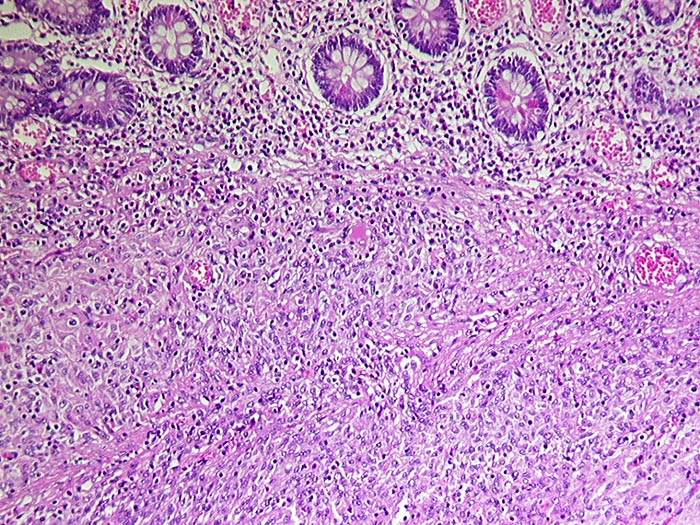

• Der Tumor besteht aus längs und quer getroffenen Faszikeln spindelförmiger Tumorzellen, welche an glatte Muskelzellen oder Schwannzellen erinnern.

• Risikostratifikation nach Miettinen und Lasota (2006): Very low risk (sehr niedriges Risiko für Metastasen oder tumorbedingte Mortalität): Lokalisation im Magen, Grösse 22mm, fehlende Mitosen.